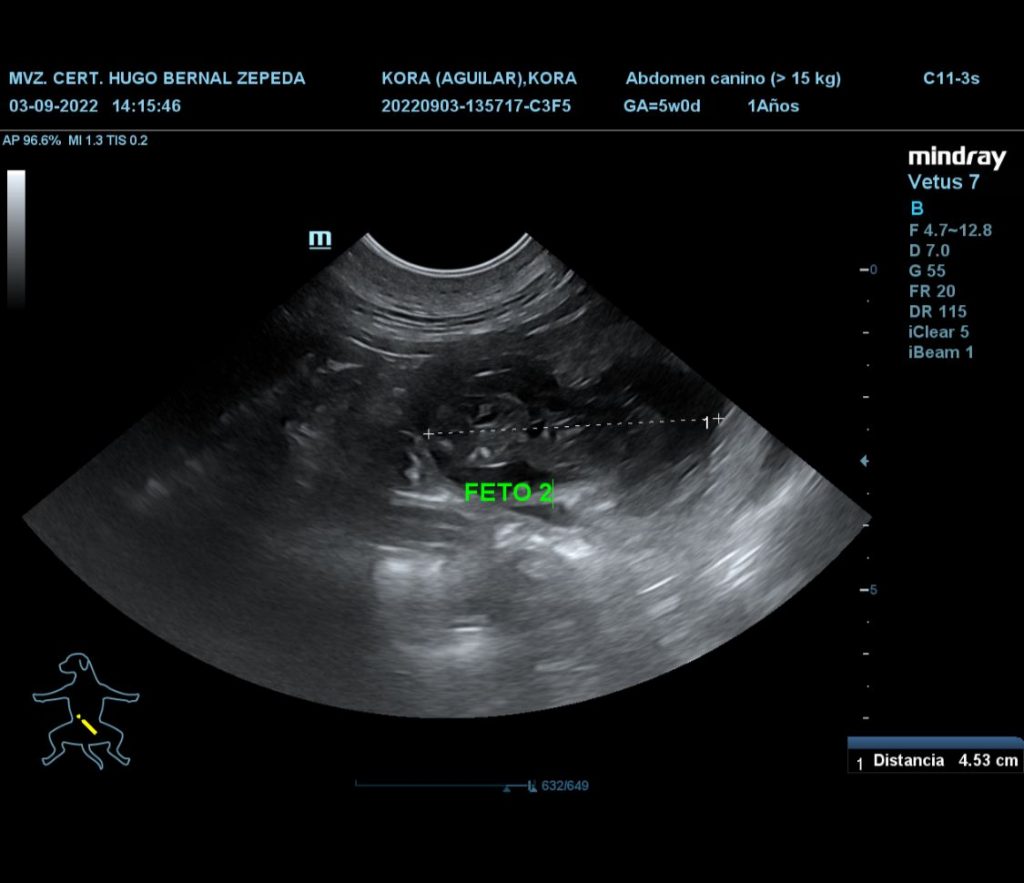

El día de hoy nos llena de dicha el informarles que la gestación de nuestra linda Kora fue confirmada por nuestro amigo y Médico Veterinario Zootecnist de cabecera Hugo Bernal Zepeda, noticia que nos ha invadido de alegría. Se estima que el nacimiento de los cachorros sea a finales del mes de Septiembre de 2020, así que muy atentos, ya que próximamente les estaremos compartiendo más detalles.